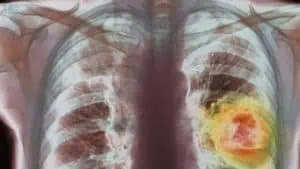

За да спре нарастването на броя на новозаболелите от злокачествени заболявания у нас, трябва да се провежда трайна профилактика, посочи проф. д-р Здравка Валерянова.

В световен мащаб има около 14 милиона нови случаи на рак и около 7-8 милиона умирания годишно. Заемаме една средна позиция, няма за какво да ви плаша.